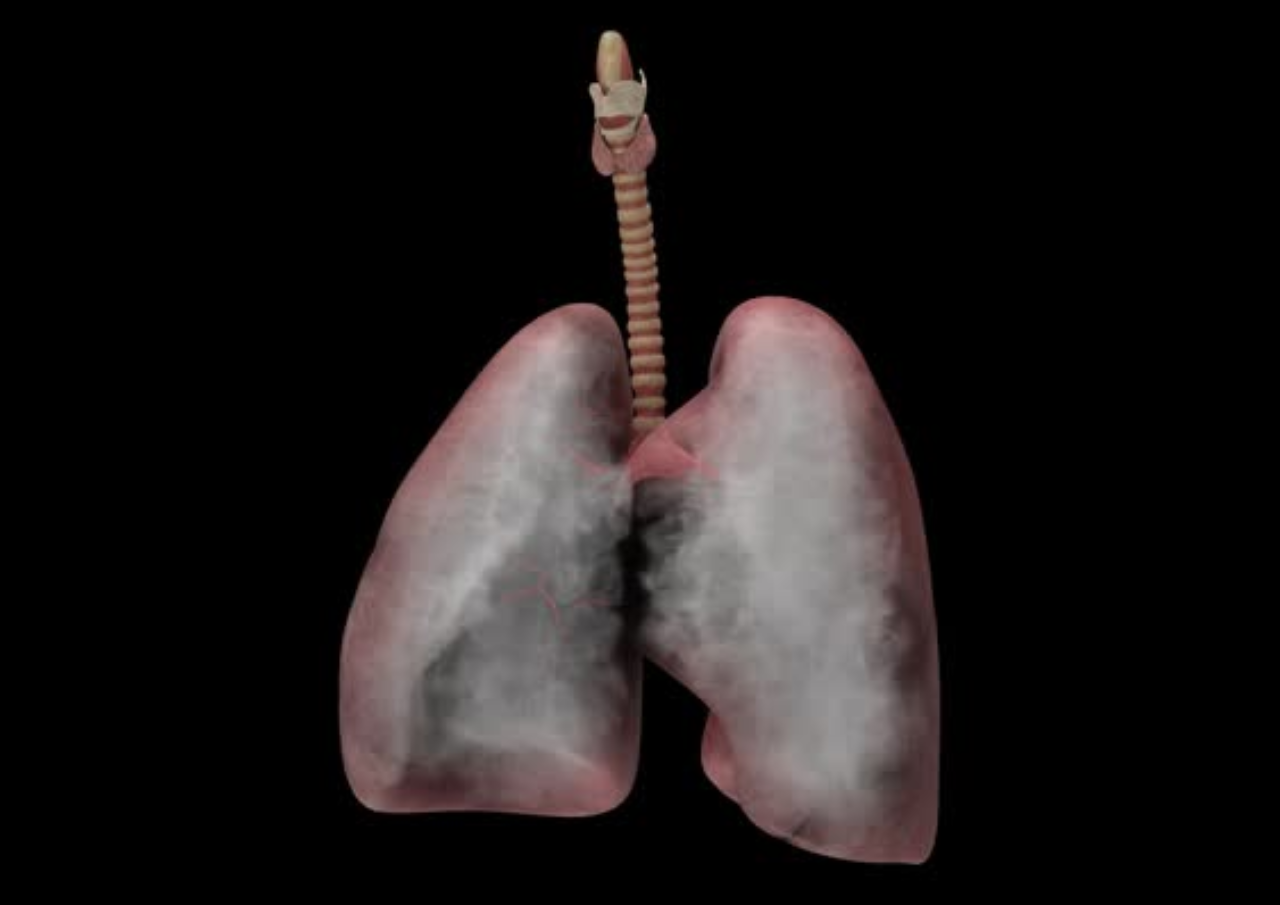

Infoseputarpati.com – Penyakit paru-paru basah mungkin familiar di telinga warga Indonesia. Kondisi yang mana paru-paru menimbulkan penumpukan cairan pada jaringan paru.

Terpapar polusi dan udara beracun dapat meningkatkan risiko terkena penyakit paru-paru basah.

Salah satu dampak berbahaya dari rokok adalah bisa menyebabkan paru-paru basah. Rokok bisa merusak pertahanan alami tubuh terhadap bakteri dan virus.